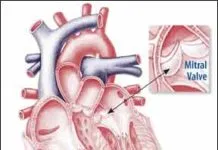

If your heart isn’t beating normally, you may be one of millions who benefit from a cardiovascular implantable electronic device (CIED). These small, battery-powered devices implanted under the skin include pacemakers for speeding up slow hearts, implantable cardioverter-defibrillators (ICDs) for preventing sudden cardiac death and cardiac resynchronization therapy (CRT) devices, which help the heart contract […]